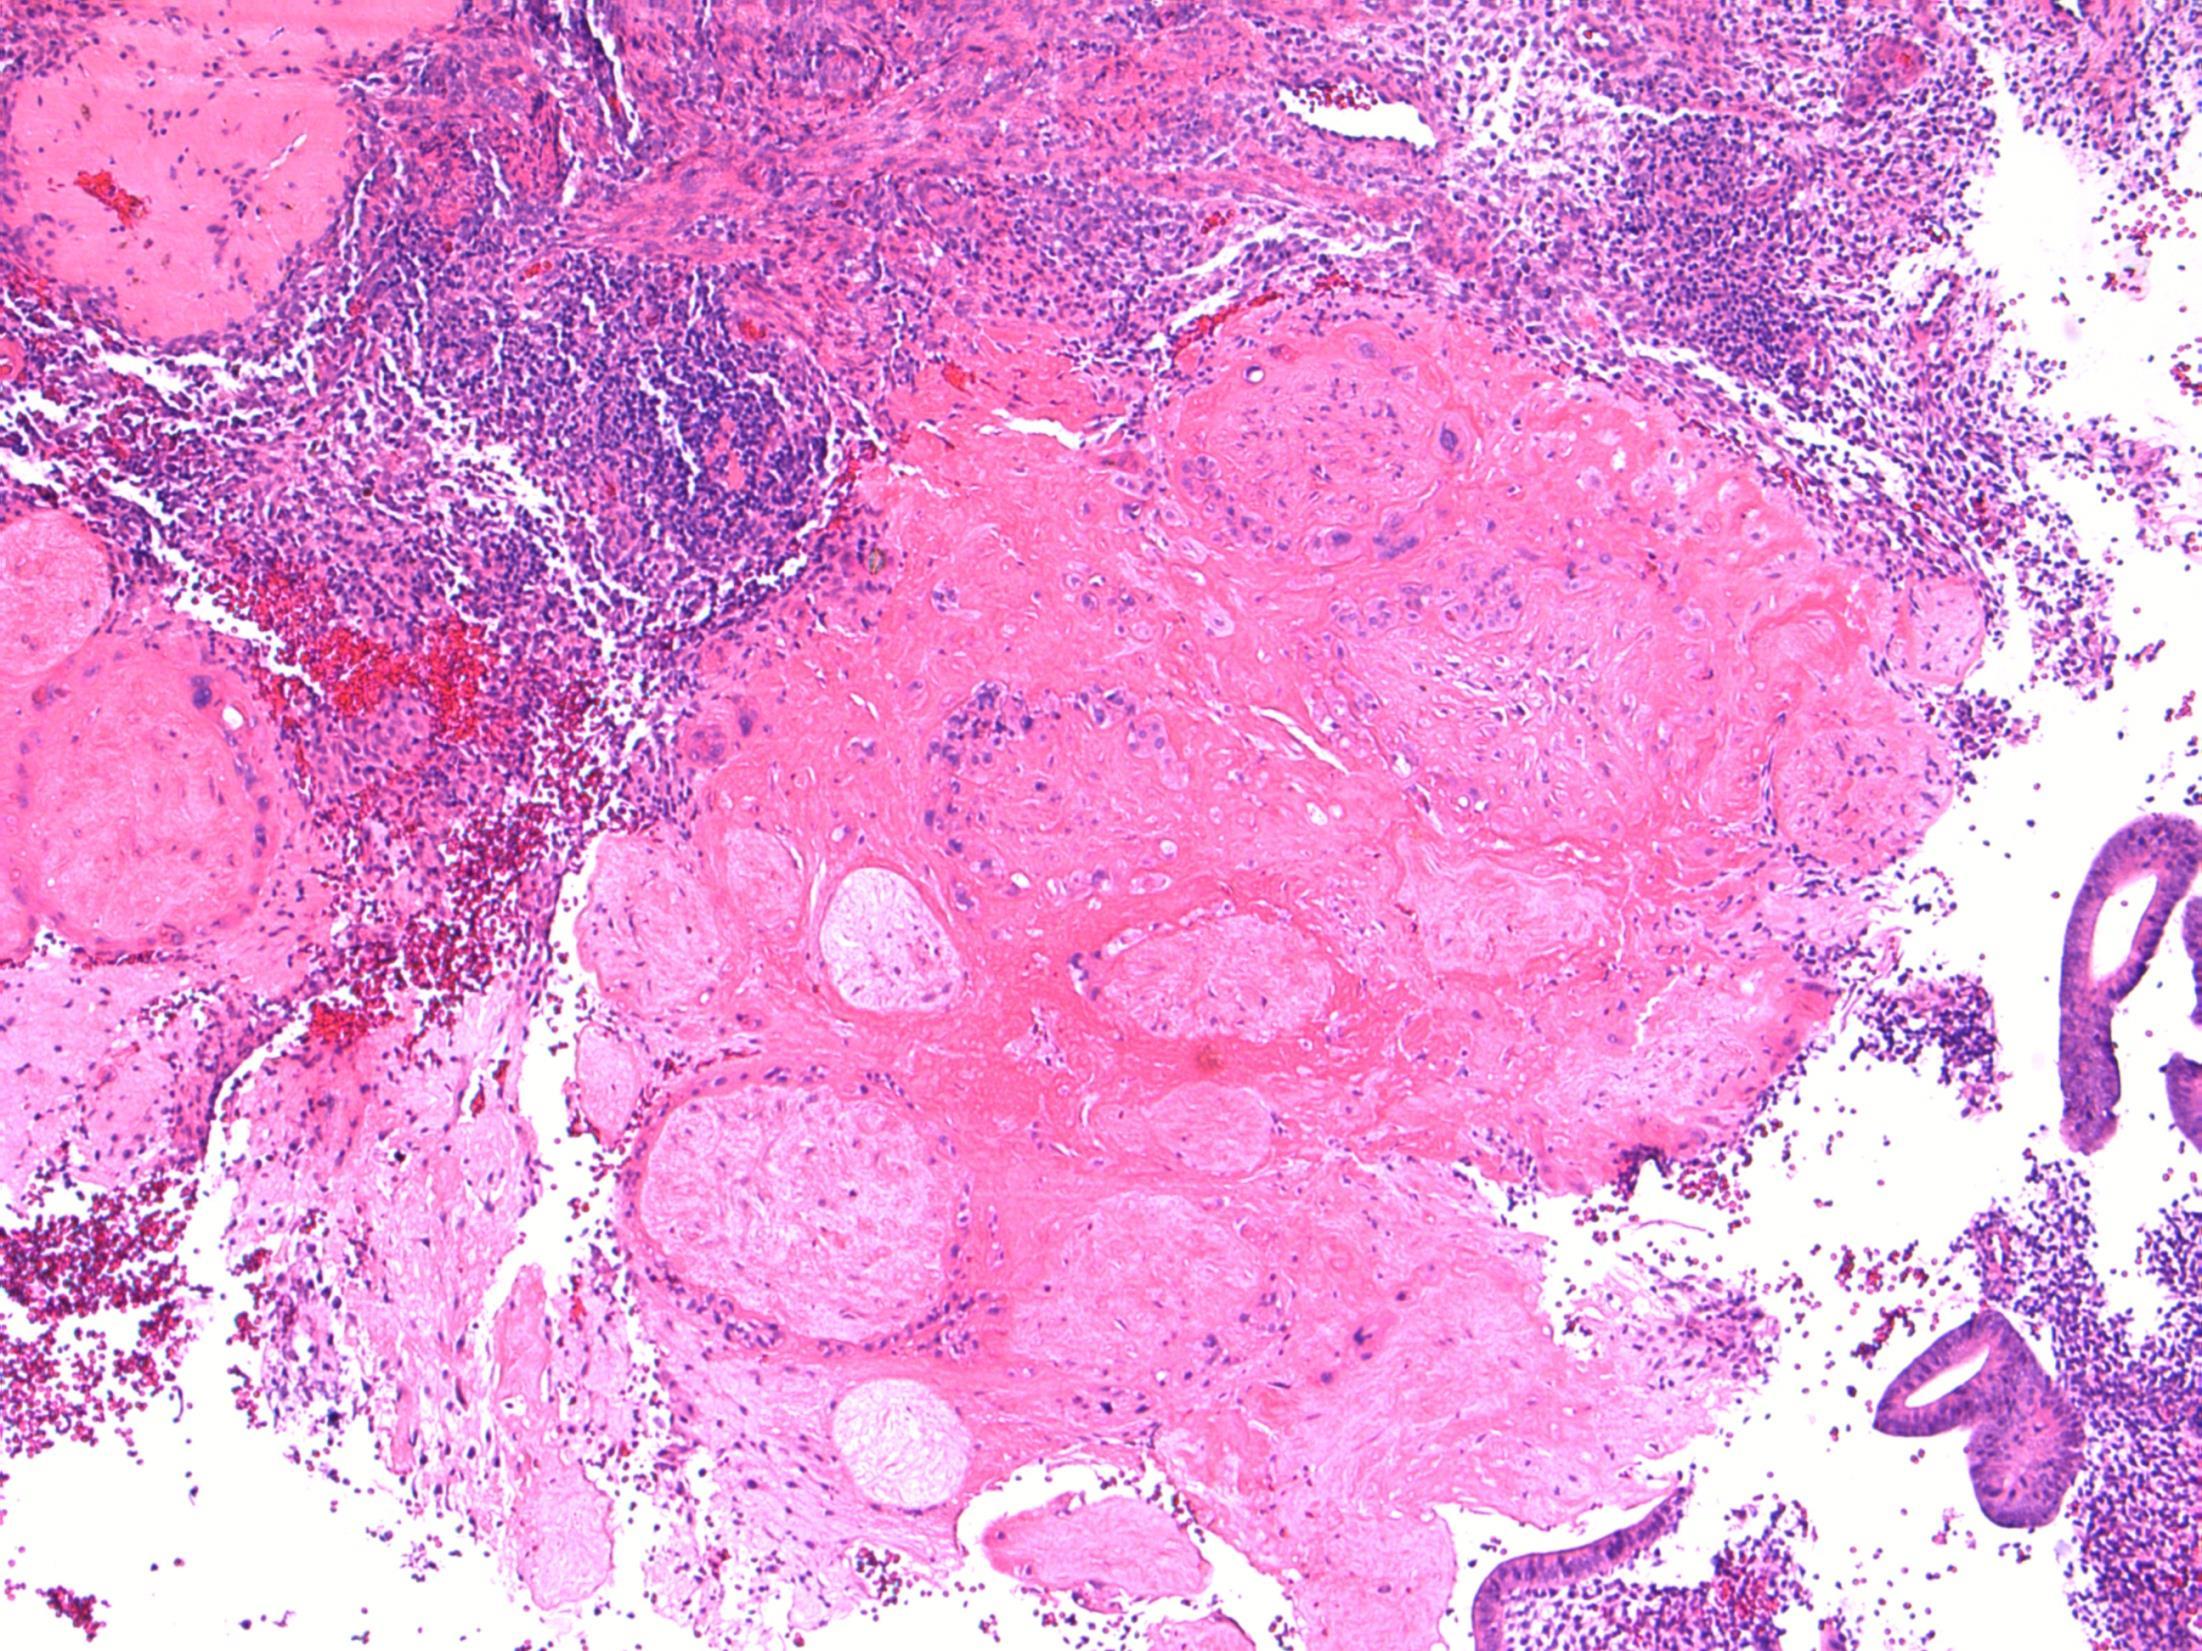

Description: Abrupt transition between tumour and epithelium. Plump papillary invaginations of thickened and infolding epithelium, hyperkeratosis. Lack of cytological atypia, suprabasal mitoses. Retraction of normal epithelium at margin. Diagnosis: Verrucous carcinoma Differential Diagnosis:

Conventional SCC – cellular atypia • Squamous papilloma – more exophtyic & branching, less keratin • Reactive inflammatory epithelial hyperplasia – most difficult but rete pegs more slender and anastomosing; no mitoses; macro correlation Plan: Correlate with previous biopsies ( often quite bland so can be inconlusive) Examine further blocks for worse areas and measure margins. Comments: In head and neck – oral cavity and larynx Often large, locally aggressive, pushing margin Better prognosis than SCC